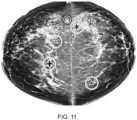

• a raw mammogram is processed and a density map (density map refers to a graphical representation where the thickness of dense tissue is mapped at each pixel intensity and displayed as a height surface, the height corresponding at each pixel (x, y) to the thicknesses of dense tissue at that location for a quantitative representation) is generated as a standardised base image.

• a density map refers to a graphical representation where the thickness of dense tissue is mapped at each pixel intensity and displayed as a height surface, the height corresponding at each pixel (x, y) to the thicknesses of dense tissue at that location for a quantitative representation

• a maximised area in a region of interest for example a rectangular area ('maximised rectangular area' is used here to describe the largest rectangular region of interest ('ROI') which fits inside the inner breast area) is then selected from the inner breast using a segmentation map ( Figure 3 ) to isolate a ROI.

• Texture features are extracted from the ROI in the density map.